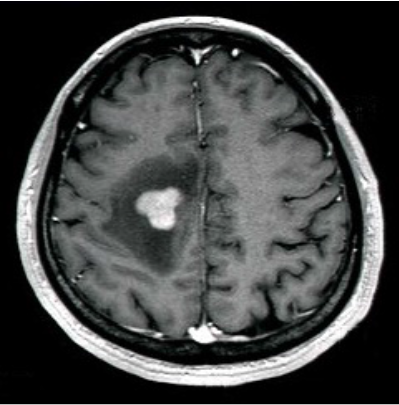

a.画像診断

脳の造影剤を用いたMRI検査で特徴的な所見が認められることがありますが、どんな形にもなりうる腫瘍としても有名です。(左図)